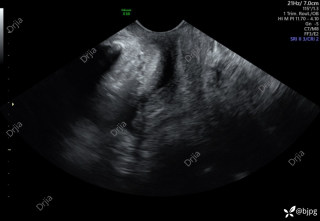

反思 | 赶高铁时一过性晕厥的老年男性

月叔打怪兽急诊科医师

昨天值班遇到的一例晕厥病例,差点漏诊,而最终的解法,始于最简单而质朴的查体。国庆中秋双节的最后一天,8号的早上8点,抢救室床旁晨交班,病人依旧是多而重,交到6床,一个刚入室不久的病人,准备去做CT,夜班医师汇报病史:69岁男性,本次因“头晕伴一过性晕厥1小时”为主诉入抢,1小时前于高铁站因即将赶不上高铁走路快时突发头晕,伴一过性晕厥,约3-4分钟后清醒,清醒后诉今晨未吃早餐,已服用降压药物,仍有头晕头痛、四肢乏力等不适,无胸闷胸痛,无畏寒发热,无咳嗽咳痰,无恶心呕吐,无肢体麻木,无视物模糊等不适,路人拨打120送至我院急诊就诊。既往高血压,长期服用氨氯地平+福辛普利,血压控制一般;糖尿病,长期